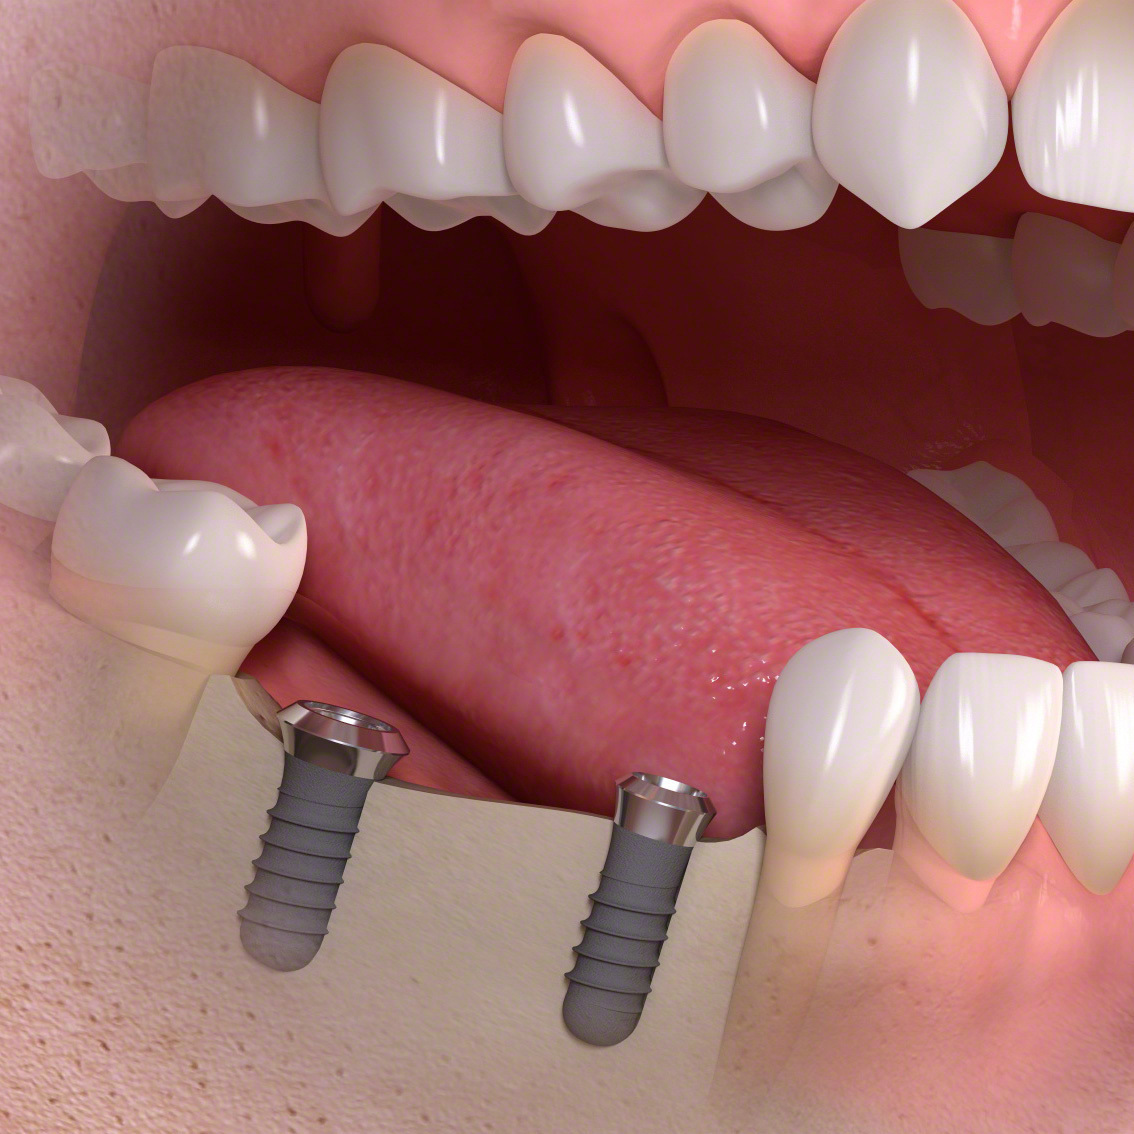

インプラント(多数歯欠損ケース)

少数の歯を失ったケース

インプラントブリッジタイプ

・インプラントとインプラントでブリッジが可能です。

数本の歯を失った。

手術でインプラントを埋める。

インプラントに土台を接続します。

ブリッジタイプの被せ物を装着します。